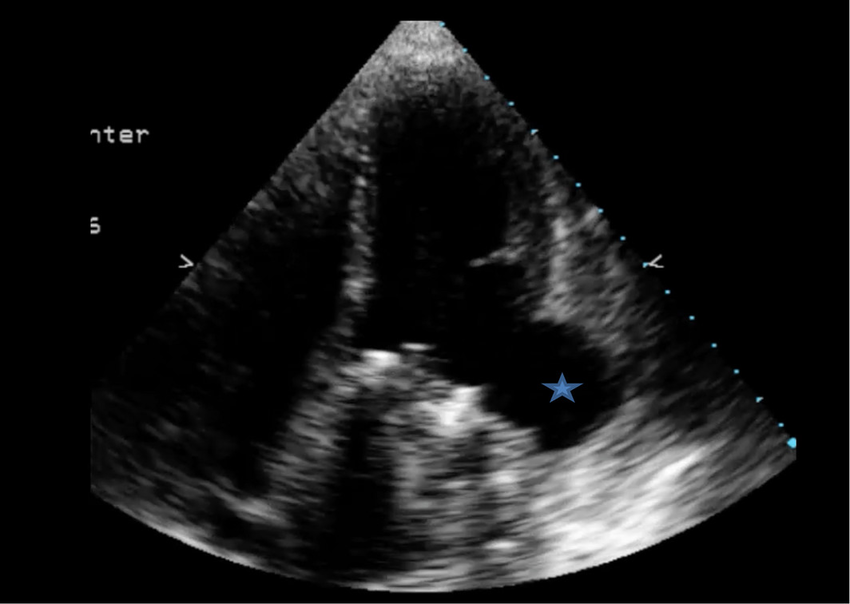

Pseudoaneurysm

What is seen in the 2D image?